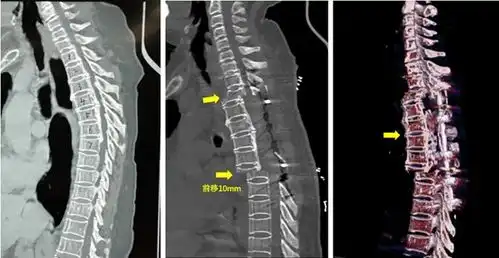

脊柱前路与后路区别 描述: 脊柱前路与后路区别 创立日期: 2025-04-28 03:25:10 图片数量: 0 pics 浏览量: 打印预览 脊柱非融合技术及其展望 天津医院小儿骨科脊柱畸形矫正策略转载 腰椎术后椎管狭窄并姿势性脊柱侧弯 青少年特发性脊柱侧弯的治疗 腰椎间盘突出腰椎间盘突出症腰椎病朋友一定要知道的 二附院实施中西部首例胸椎后路椎体opll复合物可控前移减压融合手术 腰椎滑脱,椎管狭窄症后路减压复位椎体间植骨融合术 小脚丫大健康家长必读教你选对学步鞋,为孩子打好健康基础 颈椎管狭窄前路还是后路 特色医疗脊柱结核 为什么我翘不起二郎腿也蹲不下去 新安骨科分院脊柱外科颈椎手术经典案例分享 腰椎间盘突出小常识 年轻小伙饱受脊柱结核巨大脓肿折磨,市九院专家联手祛痛除因 类别: 2025头像大全